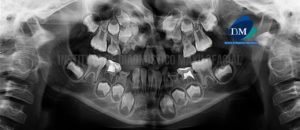

Paciente de sexo masculino de 7 años de edad acude al Instituto de Diagnóstico Maxilofacial para la realización de una evaluación imagenológica pre quirúrgica. A